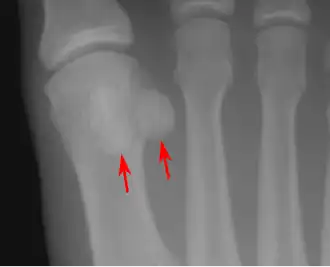

- In the foot—the first metatarsal bone usually has two sesamoid bones at its connection to the big toe (both within the tendon of flexor hallucis brevis).[10] One is found on the lateral side of the first metatarsal while the other is found on the medial side. In some people, only a single sesamoid is found on the first metatarsal bone.

- One or both of the sesamoid bones under the first metatarsophalangeal joint (of the great toe) can be multipartite – in two or three parts (mostly bipartite – in two parts).[12]

Lateral view.[11]- Bipartite medial sesamoid bone under the first metatarsophalangeal joint of the great toe of the left foot of an adult woman.